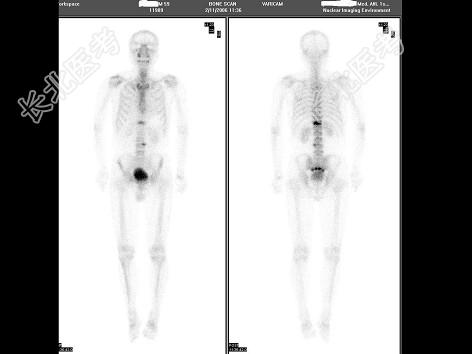

- 单项选择题男性,59岁, 腰背痛1周,1周前曾有摔跤, 无恶性肿瘤病史,骨盆16层CT未见异常, 最可能诊断为 ( )